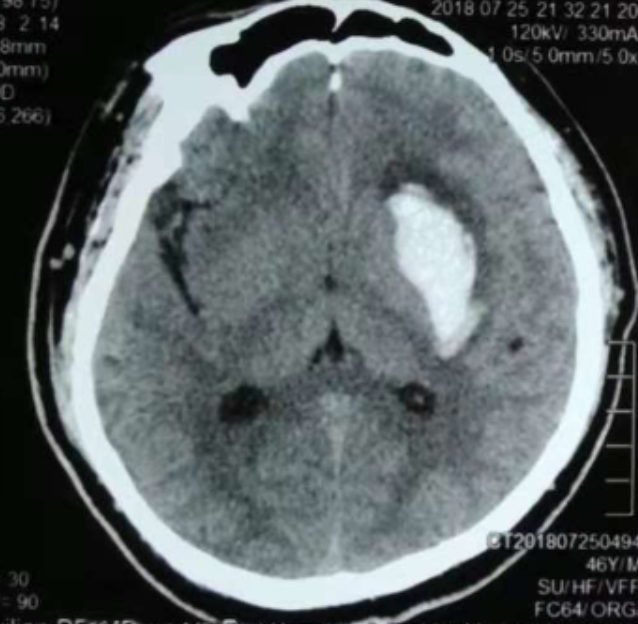

韓帥醫(yī)生借助機器人操作平臺順利抽出血性液體15ml,與術前軟件計算的血腫量完全一致,手術在30分鐘內順利完成。

術后CT:血腫腔消失